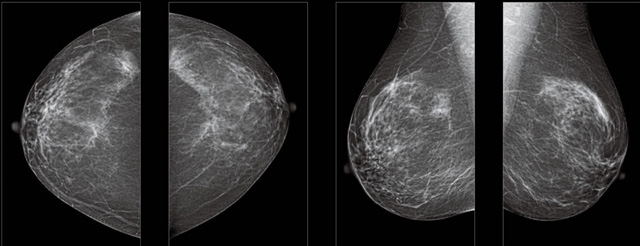

首先不同年齡階段的乳腺篩查頻次種類不一樣。青春期女性第二性征明顯發(fā)育開(kāi)始,每個(gè)月進(jìn)行自我乳腺檢查。20-30歲的女性就不推薦進(jìn)行乳腺檢查,因?yàn)槟贻p女性的乳腺組織非常緊急。鉬靶X光線等檢查的射線不能辨別腫塊跟腺體。身體就白吸收了輻射,影響了身體健康。每個(gè)月自檢一次就是在洗澡時(shí)候,對(duì)著鏡子看看乳房外觀正常,皮膚潰爛、腫塊、顏色改變、再摸一下有沒(méi)小疙瘩。乳腺高危人群,特別是有乳腺CA遺傳傾向的女性,乳腺導(dǎo)管跟小葉不典型增生,原位癌。30歲前有乳房放療的女性。乳腺癌篩查可以把年齡提前到40歲前。40到70歲的女性可以在適合的機(jī)會(huì)篩查。

采用影像檢查技術(shù)來(lái)發(fā)現(xiàn)疑似特定病檢查跟人群的普查。一到兩年進(jìn)行一次X光線的乳腺檢查。記過(guò)是C或者D型,可以加上B超協(xié)同。還可以一年一次核磁共振MRI檢查。70歲以上的女性認(rèn)為絕經(jīng)的女性是比較安全的。實(shí)際上也有乳腺癌的風(fēng)險(xiǎn)。65歲以上風(fēng)險(xiǎn)也很大。也是需要進(jìn)行機(jī)會(huì)性篩查。